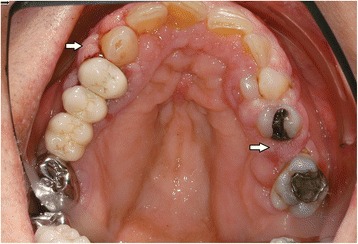

In the intraoral examination, alterations of the gingival volume were observed. Plaque control was poor since handling with the toothbrush was too difficult for the patient. Additionally, we noted the absence of petechia on the buccal and oral gingiva in the upper as well as in the lower jaw and bleeding in the buccal area of 13–15. (Figs. 1 and 2). She described intraoral pain and was handicapped during food intake. In the orthopantomogram the patient showed an impacted canine, furcation involvement of the first upper molars, and horizontal bone loss according to the age (Fig. 3). Thus, the gingival volume appeared uncommon.

Fig. 1.

Photographical Image of oral lesion at initial presentation

Fig. 2.

Photographical image of the oral lesion at initial presentation